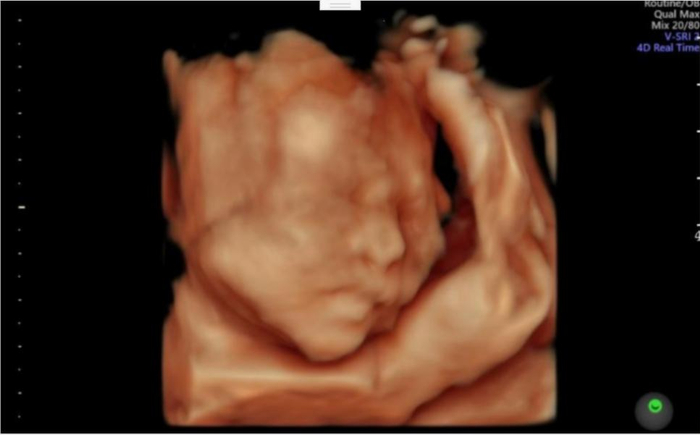

为了进一步明确存活胎儿的健康状况,小王严格遵照陆主任的医嘱做了产前诊断。很幸运,存活的那个胎儿羊水穿刺结果提示正常;胎儿的四维彩超和心脏彩超也是正常的。最终,在浙大邵逸夫医院生殖医学中心、超声科、产前诊断团队的共同保驾护航下,小王在2023年6月顺利剖宫产诞下一个健康的宝宝。